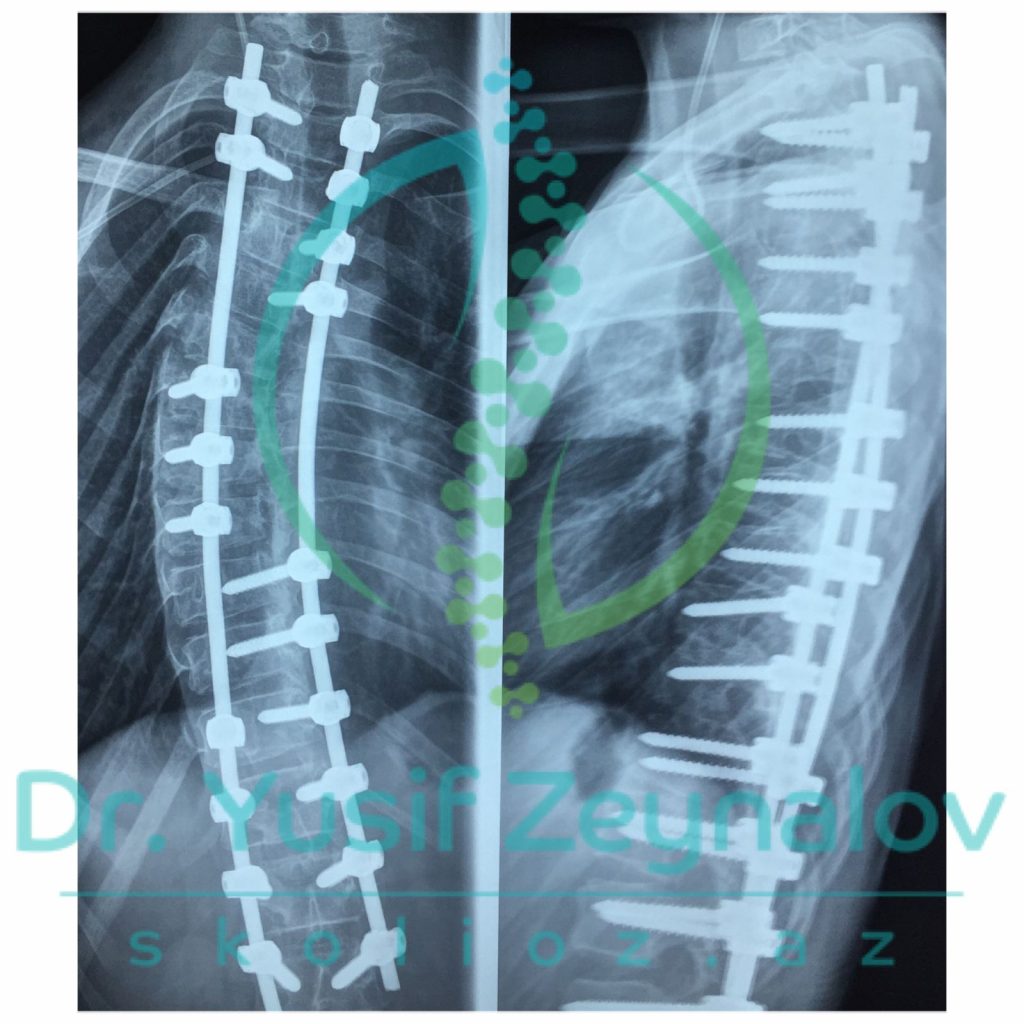

İdiopatik Skoliozlar Səbəbi bəlli olmayan skoliozlardır. Lakin bu skoliotik deformasiyaların yaranma faktorları olduqca çoxdur. İdiopatik skoliozlar zamanı müasir skolioz cərrahiyyəsinin əsasında müasir implantalogiya metodikaları, müasir implantlar, naviqasion sistemlər və 3D modelləşdirmə dayanır. Müasir implantlar və naviqasion sistemlər əvvəllər müalicəsi imkansız hesab edilən ən ağır deformasiyaların belə cərrahi əməliyyatlarını mümkün etmişdir.

-Müasir implantasiya metodikaları və implantlar sayəsində daha kiçik kəsik və daha kiçik onurğa nahiyyəsinin implantasiyası ilə skolioz korreksiyasının aparılması mümkün olmuşdur. Daha az onurğa nahiyyəsində aparılan implantasiya onurğada əməliyyat sonrası hərəkət məhdudluğunun olmamasını təmin edir. Buna baxmayaraq müasir onurğa cərrahiyyəsində onurğanın hərəkətli nahiyələrində əməliyyat zamanı dinamik rodlardan istifadə edirik. Əməliyyat sonrası bir müddət sonra əksər idman növləri ilə məşğul olmaq mümkündür.

-Skolioz əməliyyatları zamanı sinir və onurğa beyni zədələnmələri və bu fonda mümkün ola biləcək iflic riskinin qarşısını alma məqsədi ilə müasir skolioz cərrahiyyəsində naviqasion və neyromonitarizasion sistemlərdən istifadə edilir. Bu da iflic riskini 0.1%-in altına endirmiş olur.